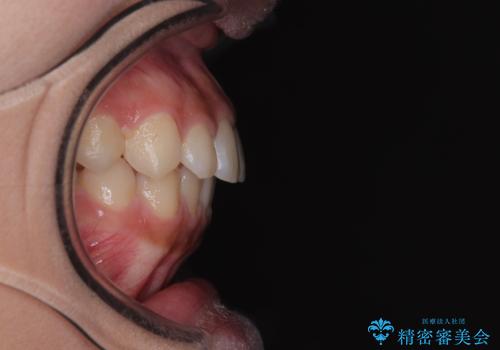

気になるすきっ歯を短期間で改善 インビザライン矯正

- 前歯の隙間を気にして来院された患者様です。

口元の突出感があり、小臼歯4本を抜歯して口元を引っ込める矯正治療も提案しましたが、本人は口元の突出感は気になっていないとのことで、インビザラインにて隙間やデコボコを改善することとしました。

軽度の歯列不正であったため、廉価版のインビザライン・モデレートパッケージにて治療を終えることができました。